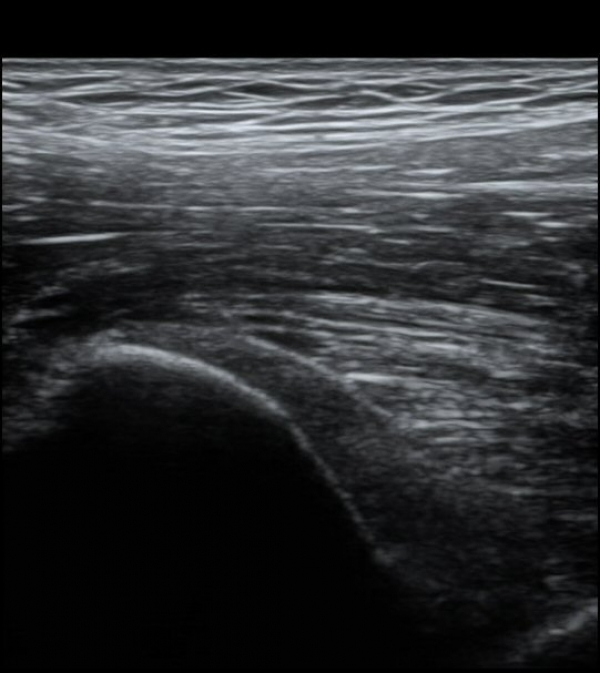

ŽÃËÀÚ¸¦ Á¶±Ý ³»ÃøÀ¸·Î À̵¿ÇÏ´Ï ÈûÁÙÀÇ °í¿¡ÄÚ°¡ ¼Ò½ÇµÇ¾î º¸ÀδÙ(»çÁø 2, 3)

ÀÌ º´Àû º¯È­´Â Á¤»óÃø(»çÁø 6, 7)°ú ºñ±³ÇÏ¸é ¶Ñ·ÈÇÏ´Ù.)